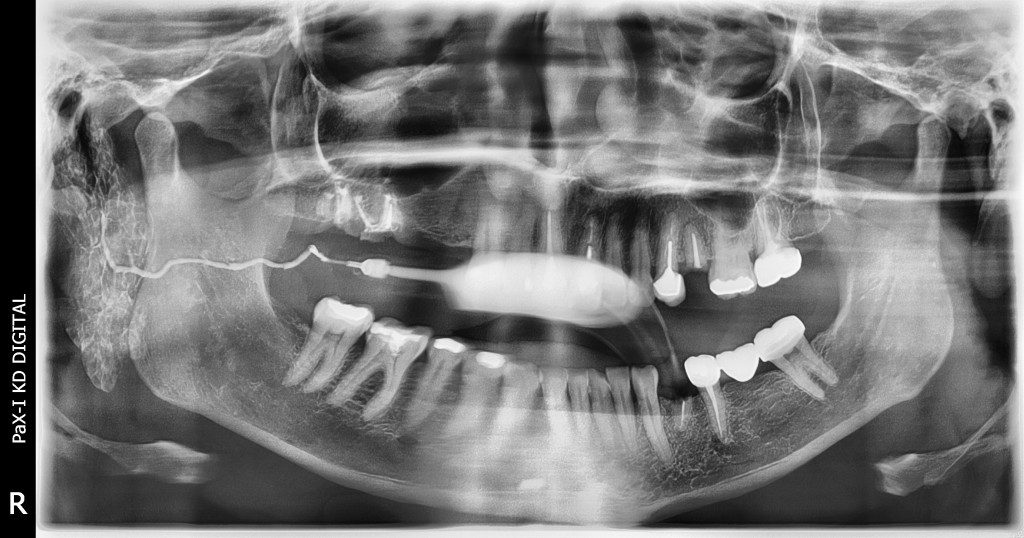

SIALOGRAFIA

• Es un estudio radiólogico en donde se utilizan medios de contraste.

• Te permite descartar o detectar alteraciones anatómicas o patológicas localizadas en los conductos salivales y determinar el lugar preciso de la alteración.